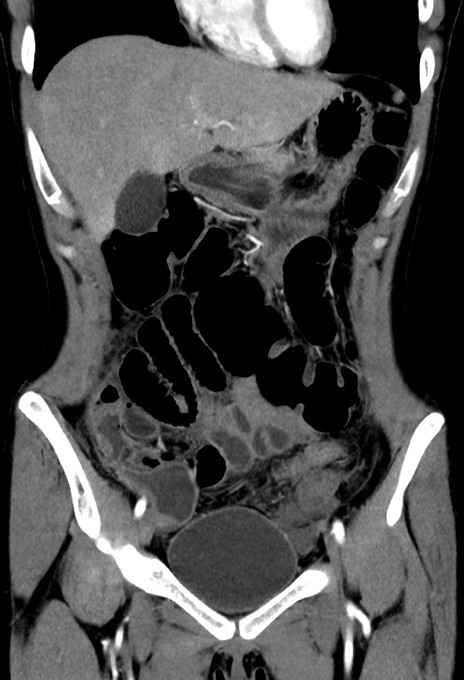

症例17(冠状断像)

【症例】20歳代女性

【主訴】嘔吐、下腹部痛

【現病歴】昨日夕食後に嘔吐し下腹部痛が出現。本日になっても嘔吐持続し改善しないため来院。

【身体所見】意識清明、BT 37.2℃、BP 108/67mmHg、腹部:平坦、やや硬、下腹部正中から右にかけて圧痛あり、反跳痛軽度あり、tapping pain(+)。

【データ】WBC 13600、CRP 14.94